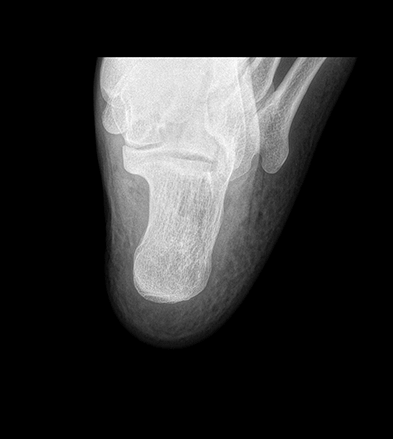

平板探测器

超高像素

高清点片